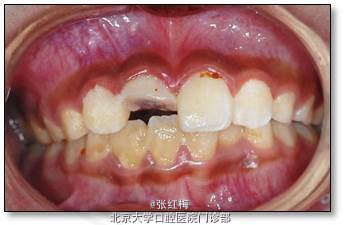

11牙冠龈1/3折断,牙髓暴露约6×1mm2,灰紫色,略有增生,叩(±),不松,龈未见异常,

21牙冠龈1/3釉质横形隐裂,叩痛(-),不松,冷测同正常对照牙,龈未见异常;

11、21正中牙合及前伸牙合未见明显牙合创伤;